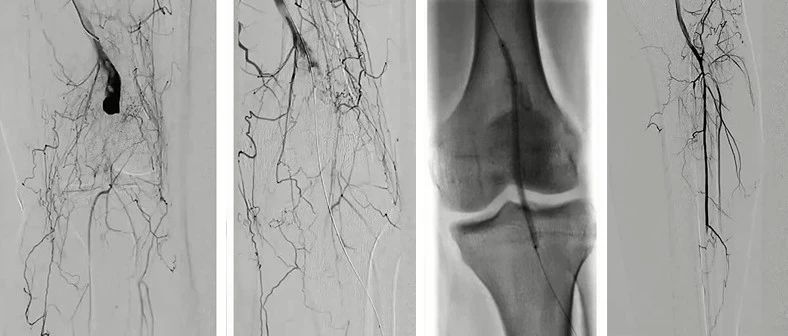

2022 CEC 手术精选 | 熊江:脉管炎腘动脉假性动脉瘤的覆膜支架植入